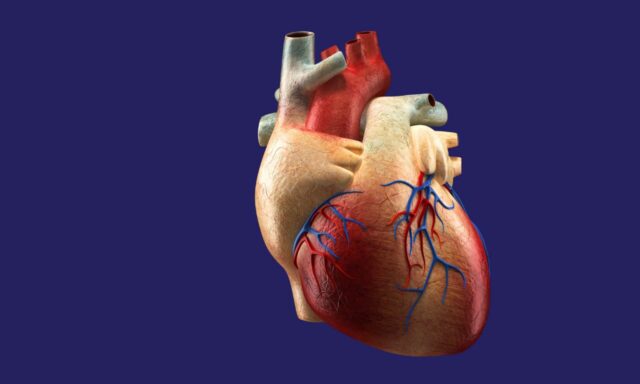

急性冠状动脉综合征(ACS)是冠状动脉疾病的一种表现形式,是用来描述一系列与心脏血流量突然减少有关的病症的总称。 流向心脏的血液突然减少会导致心肌受损。

病理机制

冠状动脉综合征通常是由于冠状动脉中的斑块破裂导致血栓形成,从而部分或完全阻断血流。